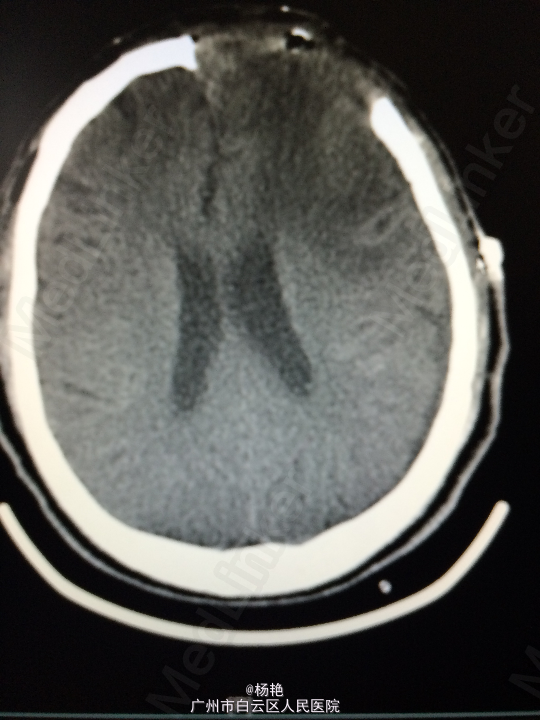

主诉:反复头痛2年加重1周 病史:患者诉两年前无明显诱因反复出现头晕头痛不适,近一周来症状加重,无恶心呕吐、无行走不稳、肢体乏力、意识障碍等。遂至当地医院诊治,行头颅CT、MR检查均提示颅内占位,良性可能性大,考虑脑膜瘤。今患者为求进一步治疗而入我院。

查体:神经系统查体未见明显异常 辅助检查:头颅MR提示:左侧额叶区域较大类圆形肿物,多考虑脑膜瘤可能;大脑前动脉及中动脉受压,中线偏移。